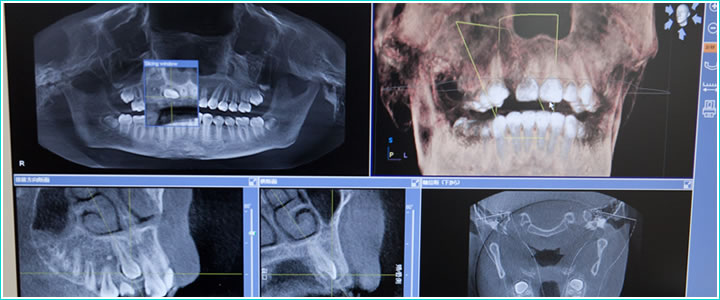

診査・診断/治療計画

お口全体の状況やインプラントを埋入する部分の骨量など調べるため、診査・診断を実施。診査・診断結果を基に適切な治療計画を立てます。